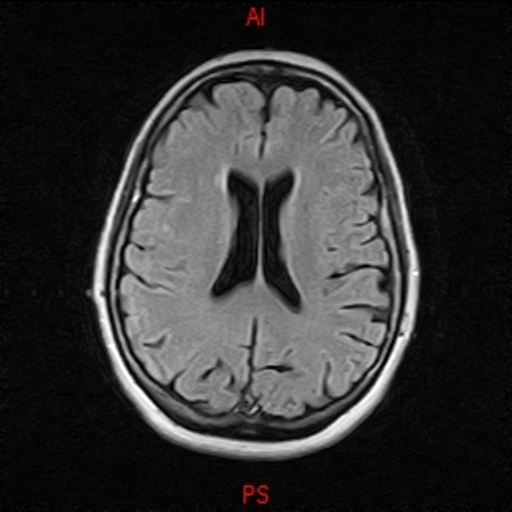

• Resonancia NORMAL CRANEAL T2 AXIAL

• Resonancia NORMAL CRANEAL T1 AXIAL